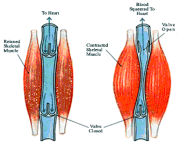

| 07:57, 15 בנובמבר 2012 | וריד115.png (קובץ) |  |

85 קילו־בייטים | Motyk | 1 | |

| 07:58, 15 בנובמבר 2012 | וריד215.png (קובץ) |  |

10 קילו־בייטים | Motyk | 1 | |